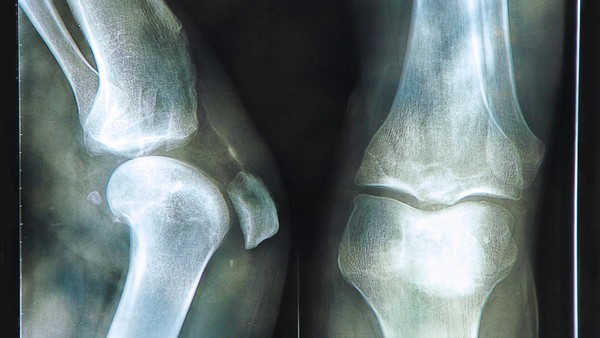

类风湿关节炎(Rheumatoid Arthritis,RA)是一种慢性炎症性自身免疫疾病,主要表现为关节疼痛、肿胀、僵硬和功能障碍。这种疾病通常会影响多个关节,最常见的是手部和脚部的关节,但也可能累及其他器官和系统。类风湿关节炎的预后情况取决于多种因素,包括早期诊断、治疗及管理的效果、患者的整体健康状况以及遗传和环境因素等。 早期诊断和治疗对于类风湿关节炎患者的预后至关重要。通过尽早采取药物治疗、物理治疗和生活方式管理措施,可以有效减轻疼痛、控制炎症、减缓关节损伤的发展,并改善患者的生活质量。治疗的目标是尽可能减少疼痛和炎症,防止和减缓关节损伤,降低残疾率和提高生活质量。 尽管类风湿关节炎是一种慢性疾病,但随着医疗技术和治疗方法的不断进步,许多患者可以有效控制疾病的发展,并保持相对正常的生活。并非所有患者的预后都是一样的,有些患者可能会出现疾病加重、关节损伤加重、残疾甚至早逝的情况。 除了治疗外,患者的生活方式也对预后起着至关重要的作用。保持适当的锻炼、合理的饮食、充足的睡眠、减轻压力、避免吸烟等,可以帮助患者控制病情、增强抵抗力和减缓疾病进展。 总的来说,类风湿关节炎的预后是一个复杂的问题,受多种因素的影响。通过早期诊断、早期治疗、合理管理和积极的生活方式,许多患者可以有效控制疾病的发展,维持相对良好的健康状况,享受高质量的生活。每个患者的情况都是独特的,因此在治疗和管理过程中应该根据个体特点制定个性化的治疗方案,以期获得最佳的预后效果。